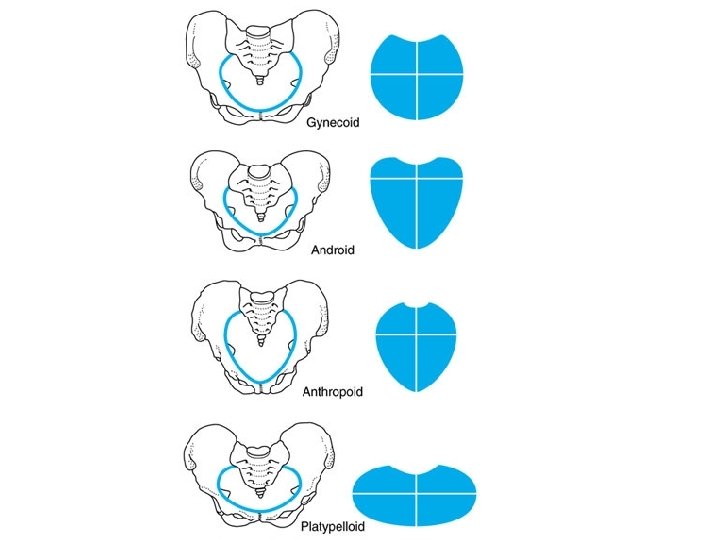

Bony pelvis • Composition: formed by paired hip bones, sacrum, coccyx, and their articulations • Two portions – Greater pelvis – Lesser pelvis • Terminal line ( pelvic inlet): formed by promontory of sacrum, arcuate line, pectin of pubis, pubic tubercle, upper border of pubic symphysis • Pelvic outlet: formed by tip of coccyx, sacrotuberous ligament, ischial tuberosity, ramus of ischium, inferior ramus of pubic symphysis

Anatomy: Bones of Pelvis • • • Sacrum Coccyx Innominates (2) Ilium Ischium Pubis